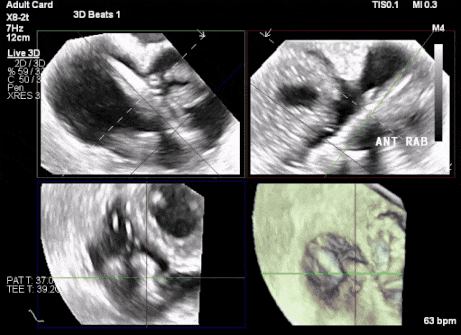

術(shù)前超聲顯示三尖瓣重度反流合并拴系

術(shù)中TEE成像困難,偽影干擾